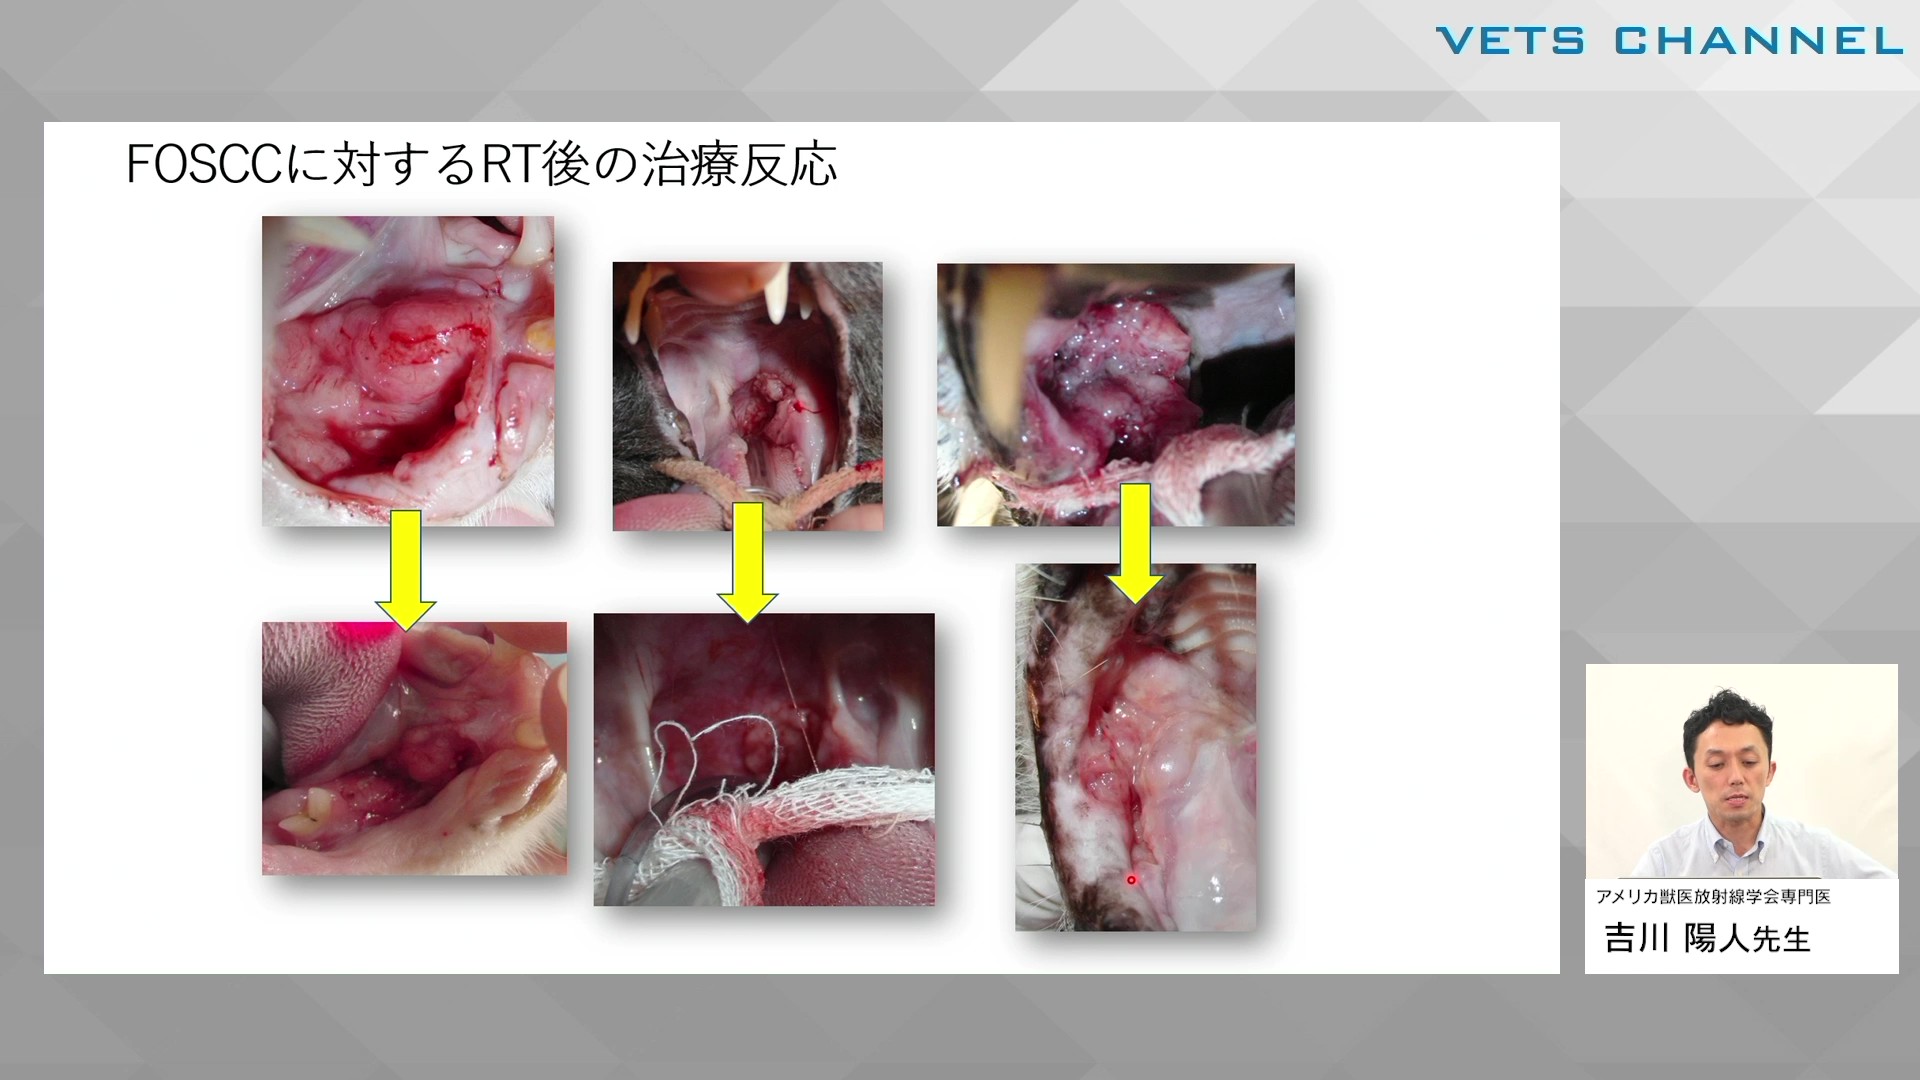

扁平上皮癌とその治療 放射線療法の適応と有効性

吉川 陽人先生(B.V.Sc,Ph.D.,アメリカ獣医放射線学会専門医)

扁平上皮癌とその治療 放射線療法の適応と有効性

吉川 陽人先生(B.V.Sc,Ph.D.,アメリカ獣医放射線学会専門医)

扁平上皮癌とその治療 放射線療法の適応と有効性

吉川 陽人先生(B.V.Sc,Ph.D.,アメリカ獣医放射線学会専門医)